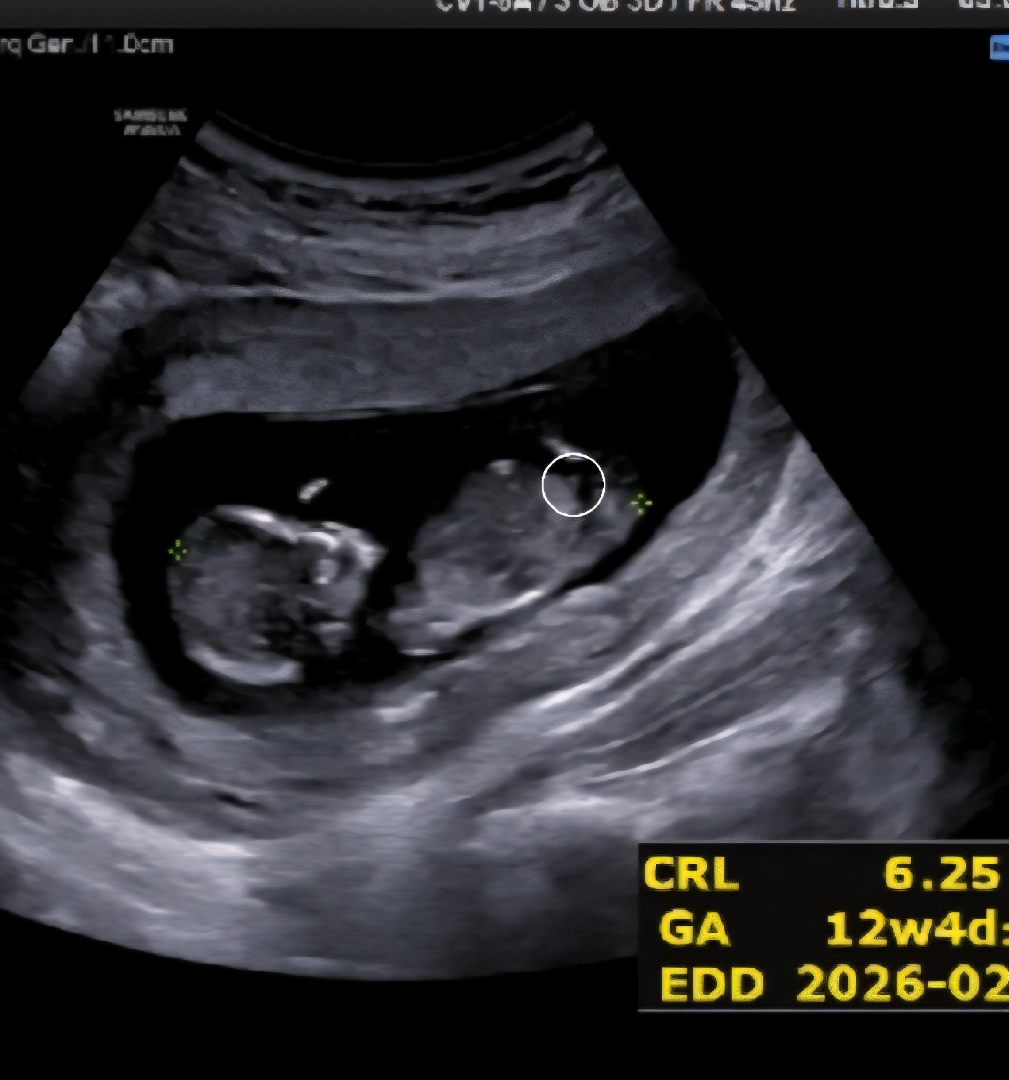

혹시 이게 🌶일까요?

요기 동그라미 친게 🌶인지 아닌지 감이 안잡히는데 봐주실분 있을까용

아뇨!! 이 각도론 안보이는 사진이에용 주수가 어떻게되세요?? 14주까지는 잘 모른대용